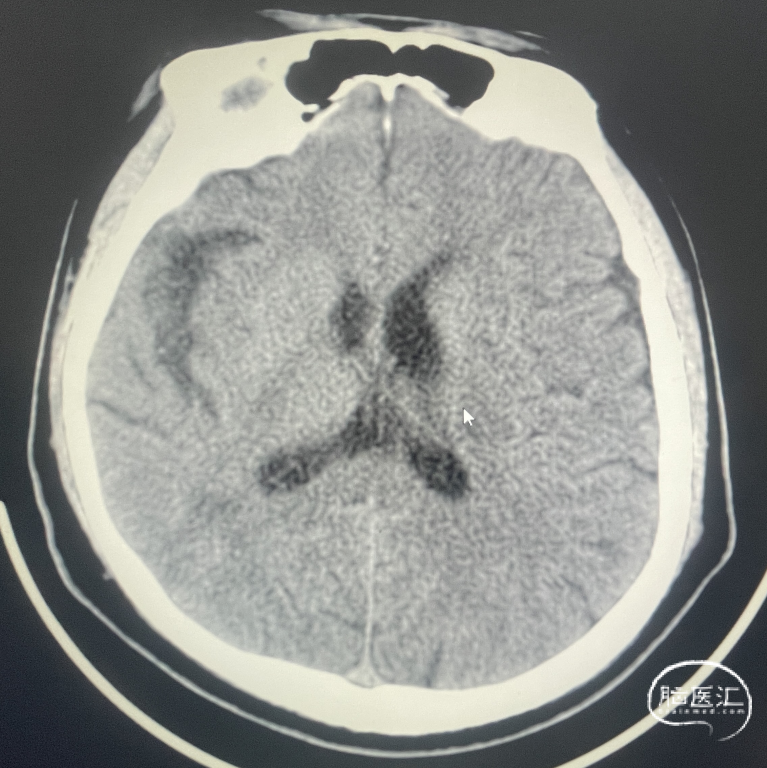

辅助检查:CT见右侧基底节区及右顶叶低密度病灶。

辅助检查:DWI:右侧大脑半球脑梗死灶;MRA检查:右侧大脑中动脉闭塞。

术后CT:术后即刻CT,以及术后24h CT。